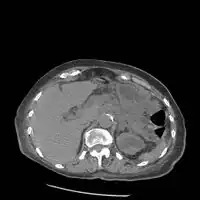

On CT scan, pancreatic and bile duct dilatation, atropy of pancreas, multiple calcifications of the pancreas, and enlargement of pancreatic glands can be found.[12]

On MRI scan, there is a low T1 signal due to inflammation, fibrosis, focal lesions, and calcifications. In those who are given with a contrast agent, there would be a higher T1 signal with late gadolinium enhancement due to compression from the fibrotic areas. The overall thickness of the pancreas will be reduced. Magnetic resonance cholangiopancreatography (MRCP) is the most useful option in accessing the pancreatic duct and bile duct.[12]

Chronic calcific pancreatitis

Acute on chronic pancreatitis